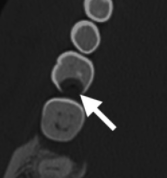

Maladie péri-apicale

- Carie > Infection de la pulpe > Mort de la Dent > Atteinte de l’Apex et lyse osseuse > Périodontite Apicale

- Inflamamtion contenue en région péri-apicale

- Spectre de lesion

- Granulome péri-apical

- Kyste péri-apical (radiculaire) (radiologiquement semblable au granulome)

- Abcès périapical

Granulome périapical